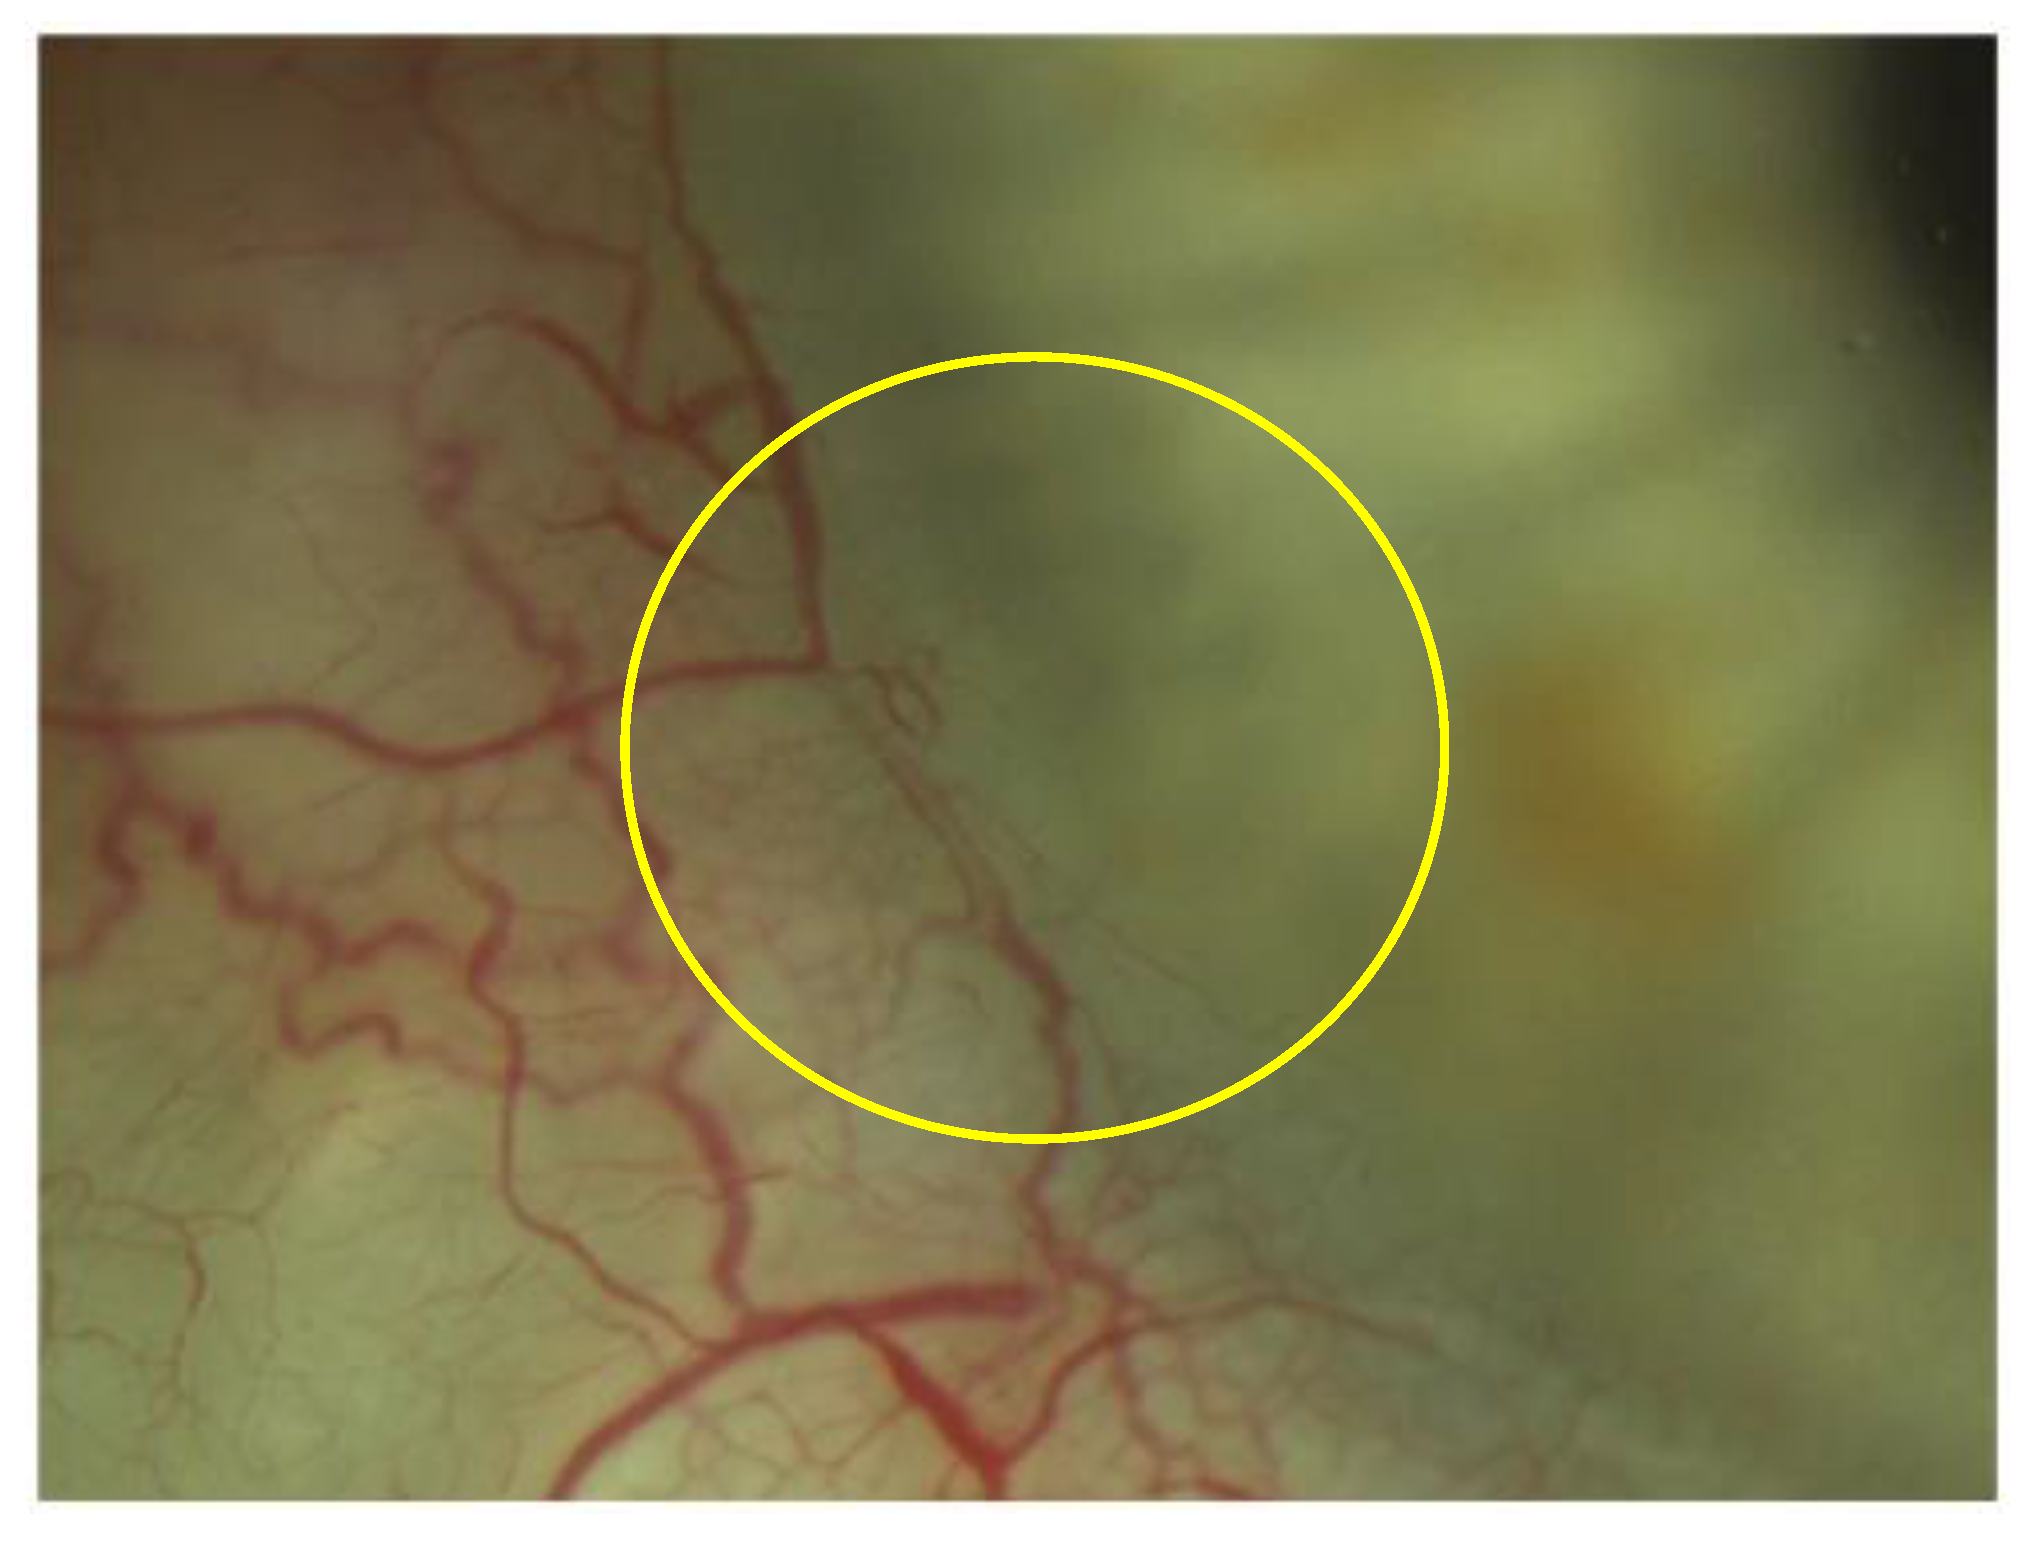

Figure 4.

Visualization of the aqueous veins 12 months after surgery (yellow circle).